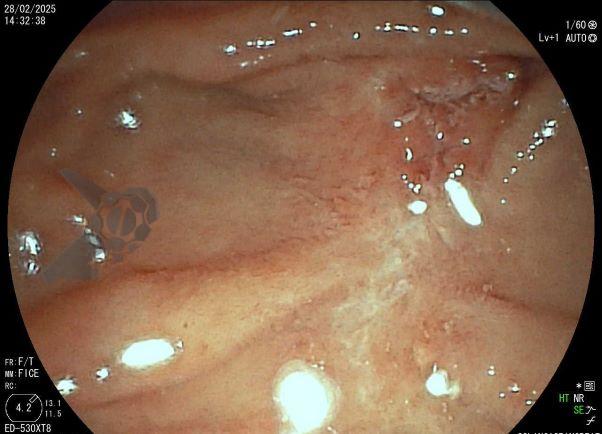

Tendo em vista quadro clínico associado a dilatação de vias biliares, foi indicada colangiopancreatografia endoscópica retrógrada (CPRE) para tratamento de possível estenose da anastomose biliar. Ao se posicionar o duodenoscópio na segunda porção duodenal, identificada lesão polipóide suspeita para adenoma de papila duodenal maior, sendo realizadas biópsias.

Diante da confirmação histológica de adenoma tubular com displasia de baixo grau, optado pelo estadiamento local através de ultrassom endoscópico (EUS), evidenciando lesão restrita a mucosa (sem sinais de acometimento de camada muscular) medindo 12×9 mm, com dilatação de colédoco até 9 mm e ausência de extensão intraductal.

Tendo em vista a visão parcial da papila duodenal maior obtida através do endoscópio de visão frontal, sugere-se que a adequada avaliação seja realizada com o duodenoscópio ou endoscópio convencional associado ao uso de cap. Embora não exista uma classificação validada para avaliação das lesões de papila, deve-se avaliar o tamanho, se há extensão da lesão para além da papila, como as lesões de crescimento lateral (LSTp). Além disso, alguns aspectos identificados correlacionam-se com maior risco de invasão da muscular como endurecimento, ulceração, friabilidade, sangramento, depressão e “nonlifting sign”4,5. O diagnóstico histológico deve ser realizado idealmente pela biopsia endoscópica; em caso de falha diagnóstica, são alternativas a biópsia por EUS ou biópsia endoscópica após esfincterotomia, de preferência com intervalo de 10 dias entre os procedimentos4. Vale ressaltar que a presença de adenoma nas biópsias endoscópicas não exclui a presença de adenocarcinoma, devido as altas taxas de falsos negativos e variável concordância entre as biópsias endoscópicas e as peças de ressecção5.